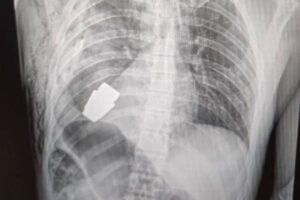

2023 01.14 爆発する可能性のあった手榴弾、医師がウクライナ兵の胸から摘出 国際ニュースまとめ ウクライナの医師が、手術を行い、兵士の胸に入った手榴弾を摘出することに成功した。 Source: Switch News もっと記事を見ていきませんか? セガ、 「タイランドゲームショウ」に初出展 新型コロナを検査できる新しいマスクを開発中:MIT他 タリバンが生放送中に、BBCの女性キャスターの電話に直接かけてきた! 【タイ】水に浸かりながら食べるお店、お客が集まり人気スポットに 意外と怖い…米でハロウィーン屋敷のコンテスト、家の前にさまざまな幽霊が並ぶ イギリスで人間が鳥インフルエンザに感染、非常に稀なケースが報告される Tweet Share Hatena Pocket Post navigation 前の記事 次の記事 関連記事 コストコがトランプ政権提訴 なぜ 台湾当局「中国軍が海峡で模擬攻撃」 外国艦船を追跡… 2026年 タイ祝日・休日カレンダー 朝日新聞社・石合編集委員に韓国のメディア賞 朝鮮通… 本当に“日本版トラスショック”は生じないのか 獲物を狙うサメや人の顔の形をした火山噴火――国際航… タイ、数十年続いた午後の酒販売禁止を一時解除 J.Y.Parkが沖縄に家族旅行→娘2人との動画も… 【Wミリオン】両学長『お金の大学』は、なぜ&…